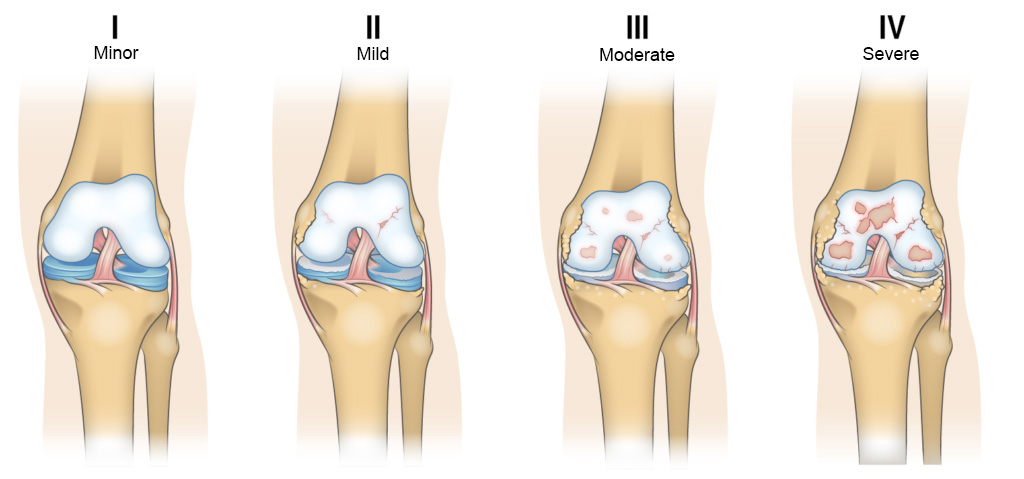

Thoái hóa khớp gối là một nguyên nhân phổ biến gây ra tình trạng lỏng khớp gối, đặc biệt ở người cao tuổi. Khi tuổi tác tăng lên, các mô sụn trong khớp gối dần bị mòn đi, làm giảm sự bôi trơn và khiến các cấu trúc khớp hoạt động không hiệu quả. Điều này dẫn đến việc khớp gối mất khả năng ổn định và dễ bị tổn thương.

Thoái hóa khớp gối có thể gây đau, làm giảm tính linh hoạt của khớp, dẫn đến khó khăn khi gập duỗi gối. Thoái hóa khớp cũng có thể gây ra sự mất cân bằng trong các nhóm cơ xung quanh khớp, làm tăng cảm giác lỏng lẻo và thiếu ổn định khi di chuyển.

Điều trị thoái hóa khớp gối tập trung vào việc giảm đau và duy trì chức năng của khớp. Các phương pháp điều trị bao gồm việc sử dụng thuốc giảm đau, chống viêm và thực hiện các bài tập vật lý trị liệu để cải thiện sức mạnh cơ bắp và linh hoạt của khớp. Một phương pháp hiệu quả khác là tiêm huyết tương giàu tiểu cầu (PRP) hoặc tiêm chất bôi trơn khớp để cải thiện khả năng di chuyển và giảm thiểu đau đớn. Trong trường hợp thoái hóa khớp nghiêm trọng, phẫu thuật thay khớp gối có thể là lựa chọn cuối cùng.